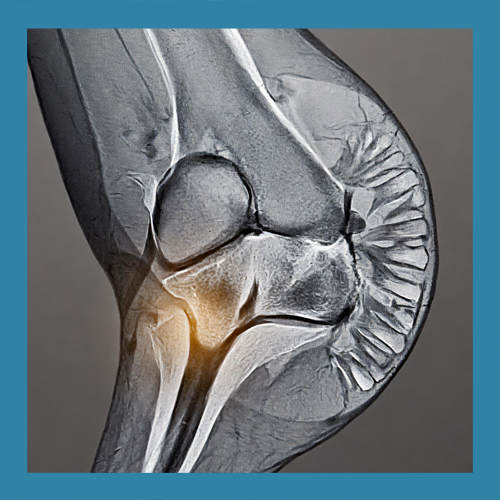

반월상 연골 파열의 치료는 손상의 위치와 정도에 따라 다르게 접근해야 합니다. 경미한 파열은 보존적 치료로 충분히 회복될 수 있지만, 심각한 경우에는 수술이 필요할 수 있습니다. 이를 정확히 판단하기 위해 MRI와 같은 정밀 검사가 필수적입니다.